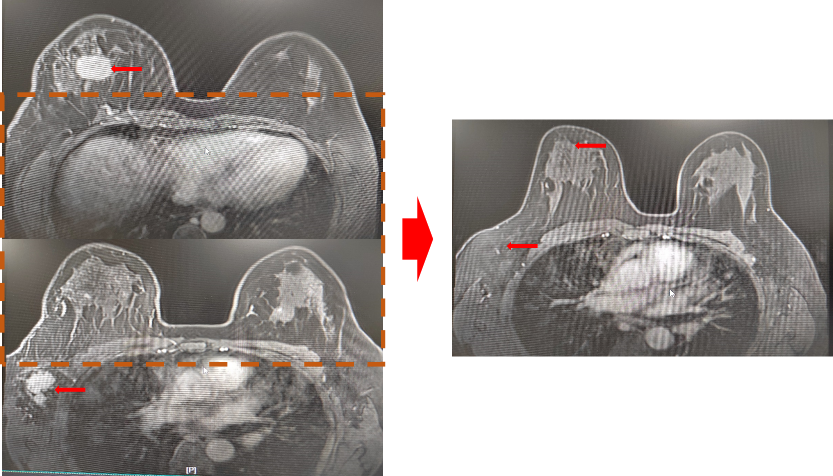

B超:右侧乳腺6点可见一大小约31×18mm低回声结节;右侧10点可见一大小约30×18mm低回声结节;BI-RADS分级:5类;右侧腋窝明显肿大淋巴结,大小约21×19mm。

图1. B超 2021.9.23

MRI:右侧乳腺肿块、结节,右侧腋窝肿大淋巴结,BI-RADS:5类。考虑右乳癌伴右腋窝淋巴结转移可能(2021-9-28)。

图3. 胸部MRI 2021.9.28